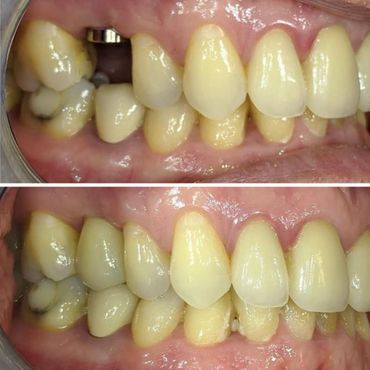

A dental implant is an artificial replacement of the root of a tooth. It is a viable option for people of all ages who are in good oral health. The implant is normally a cylinder-shaped metal post inserted and fused into the bone. A replacement tooth is then fitted onto it once it fuses into the bone. With the implant, one can eat, chew, and brush normally.